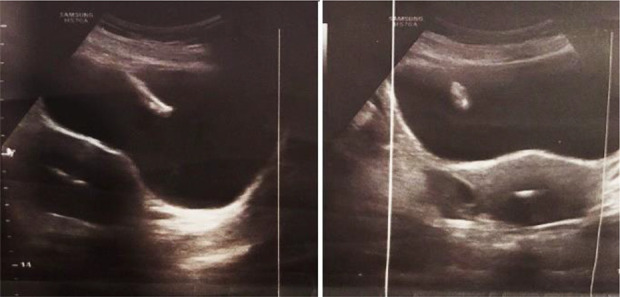

Case presentation: Our case was a 41-year-old woman whose IUD was accidentally discovered in her bladder during a routine ultrasound. The IUD has migrated from its normal position in the uterus to the bladder. The IUD was successfully removed by cystoscopy without any complications.